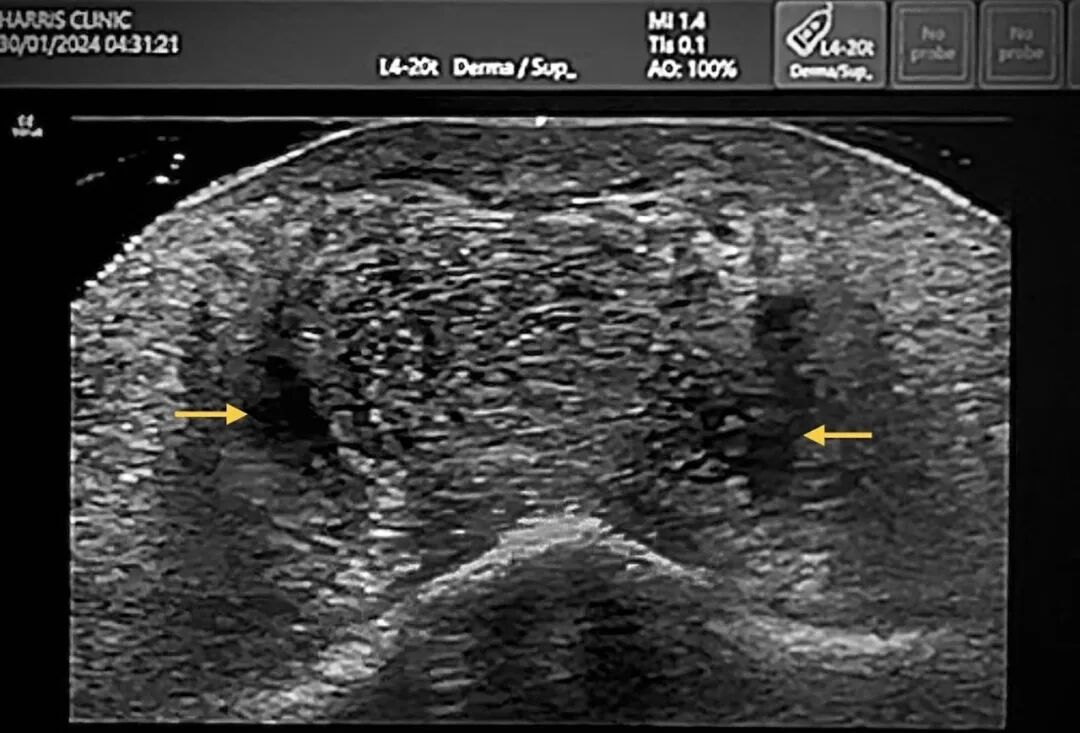

“溶解”这一表述,错误诠释了酶的作用机制,易使患者产生不切实际的预期,且当后续影像学检查显示填充剂残留时可能增加医疗法律风险。透明质酸酶仅能裂解透明质酸,无法破坏胶原蛋白、脂肪、筋膜、韧带或其他结构性组织。长期沉积的填充剂与发生病理改变的软组织深度交织,绝非简单的 “溶解与否” 模型所能概括(图5)。

图5. 颏部超声图像,示陈旧性填充剂相关继发改变,包括持续存在的透明质酸填充剂(箭头所示)、间质水肿,以及高回声纤维性间隔。